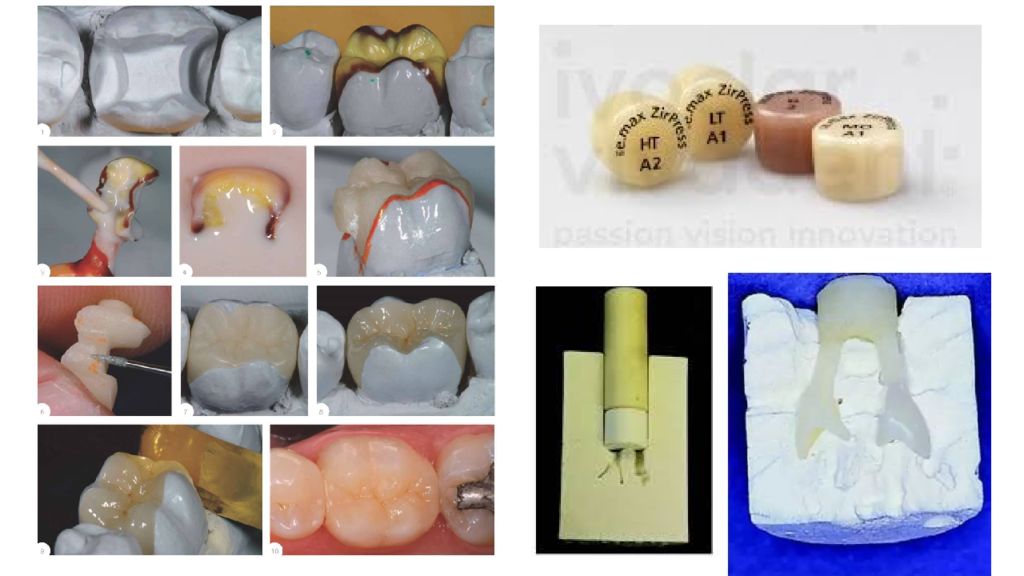

Препарирование кариозных полостей III класса: пошаговое руководство с фото

Раздел: Необычные решения